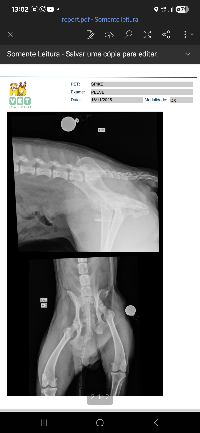

Olá, pessoal! Venho aqui pedir a ajuda de vocês para o Spike, o cachorro do meu pai, que foi atropelado por um motorista que fugiu. Mesmo sentindo muita dor, ele se arrastou até nossa casa em busca de socorro. Nos exames, o veterinário confirmou que ele fraturou seu quadril em 3 partes.

O médico veterinário explicou que o procedimento completo — cirurgia, medicamentos, exames e internação — terá um custo de R$ 5.800. Infelizmente, não conseguimos arcar com esse valor sozinhos.